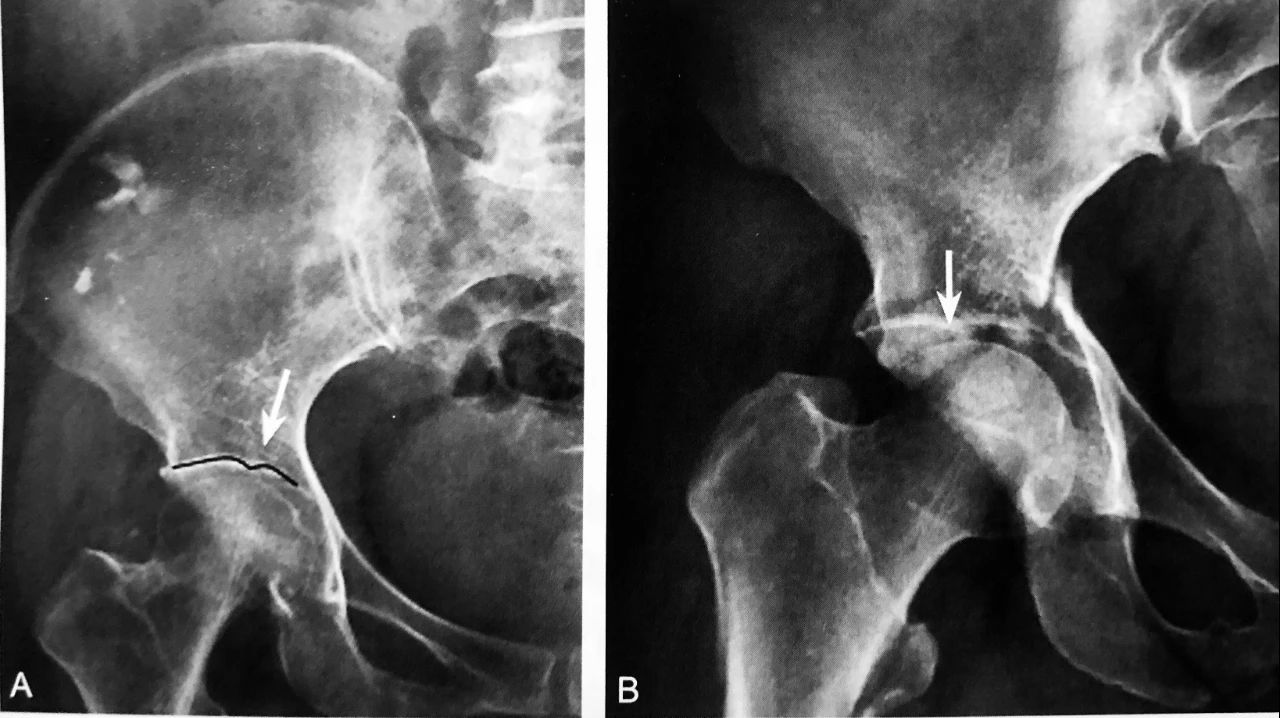

新 月 征

髋关节 X 线平片示右侧股骨头关节面下新月形透亮影,提示新月征

判读要点:

1、新月征是 III 期股骨头坏死的直接征象;

2、新月征对诊断股骨头坏死具有特异性,提示股骨头早期塌陷;3、在 X 线骨盆或髋关节正位片显示。